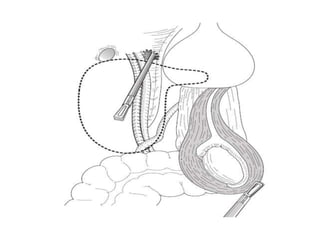

Fowler stephens orchidopexy

(open/Lap )

• If the testis is located more

than 3 cm from the

ipsilateral internal inguinal

ring, a Fowler-Stephens

procedure is typically

indicated.

• The Fowler-Stephens

technique involves clipping

and transecting the

testicular vessels.

• This procedure can be

done in one or two

stages. In addition, the

Fowler-Stephens

procedure can be

performed in open or

laparoscopic surgery.

• When this technique is performed as a single-

stage procedure, the spermatic vessels are

isolated, ligated (or clipped) and sectioned at least

3-4 cm away from the testis, allowing the testis to

be placed in the scrotum without tension.

• The testis remains viable owing to the

vascularization derived from the deferential

vessels. The main disadvantage of this single-

stage procedure is that the deferential artery might

be so small that, if it goes into vasospasm, testis

atrophy is very probable.